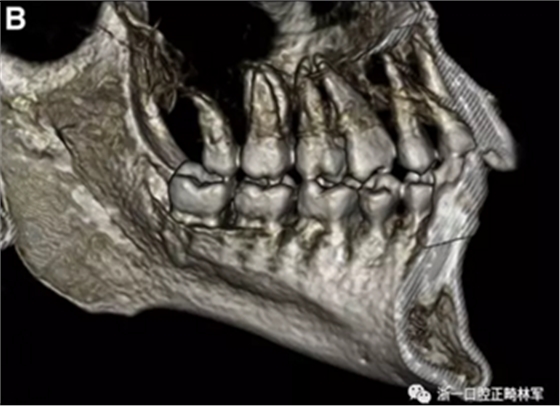

患者的上頜骨和下頜骨研究模型在最大牙尖交錯(cuò)位時(shí)確定和數(shù)字化(圖2,A),作為咬合指導(dǎo)(咬合指導(dǎo))。該數(shù)字化咬合指導(dǎo)在齦緣周圍進(jìn)行數(shù)字化修剪,以便在CBCT掃描上可以更好得可視化(圖2,B)。

圖2. A,咬合時(shí)對象研究模型的右側(cè)舌側(cè)視圖掃描將作為未來指導(dǎo);該指導(dǎo)稍后用于將懸浮的下頜骨配對到修剪的上頜骨;B,左側(cè)舌側(cè)視圖的數(shù)字化修整牙合引導(dǎo)。